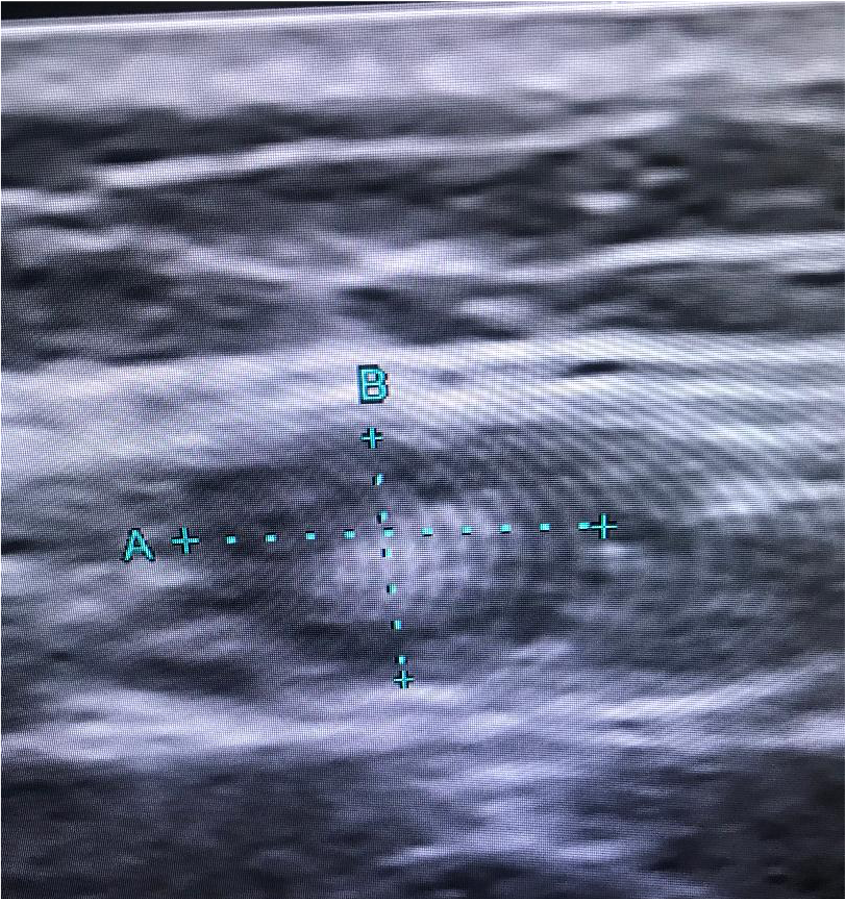

Part 3. Man in his sixties with history of papillary thyroid carcinoma (thyroidectomy). A submental 6 mm node is seen by the endocrinologist. US features are benign (oval with fat in the hilar region). Material for thyroglobulin biochemical analysis is also obtained